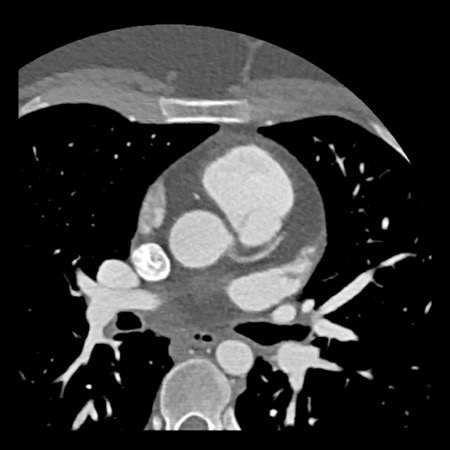

case 3 – Calcium score 0 and severe stenoses.

First, scroll through the CTA images.

How would you describe the findings on the coronary CTA?

The findings are:

- The total calcium

score of 0 indicates the absence of calcified plaque in the coronary

tree. - Severe stenosis

(70-99%) in the mid LAD and D2 branch.

Continue with the next images of the same patient…

Same patient. First, study the CTA image.

How would you describe the findings?

The coronal image shows a central low-attenuation area around the lumen

of the LAD.

This low-attenuation area is surrounded by a higher attenuation

area.

This finding is the earlier discussed napkin-ring sign, which is a high-risk

plaque feature.

This patient classifies as CAD-RADS 4A/P1/HRP.